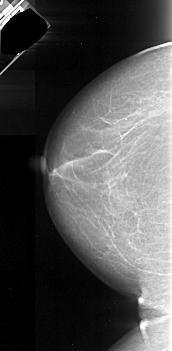

A_1048_1.LEFT_CC

LEFT_CC LINES 5251 PIXELS_PER_LINE 2566 BITS_PER_PIXEL 16 RESOLUTION 42 NON_OVERLAY

FILE: A_1048_1.RIGHT_CC.OVERLAY

TOTAL_ABNORMALITIES 1

ABNORMALITY 1

LESION_TYPE MASS SHAPE IRREGULAR MARGINS ILL_DEFINED

ASSESSMENT 4

SUBTLETY 5

PATHOLOGY MALIGNANT

TOTAL_OUTLINES 1

BOUNDARY